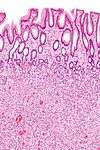

Micrograph of a Peutz-Jeghers colonic polyp - a type of hamartomatous polyp. H&E stain.